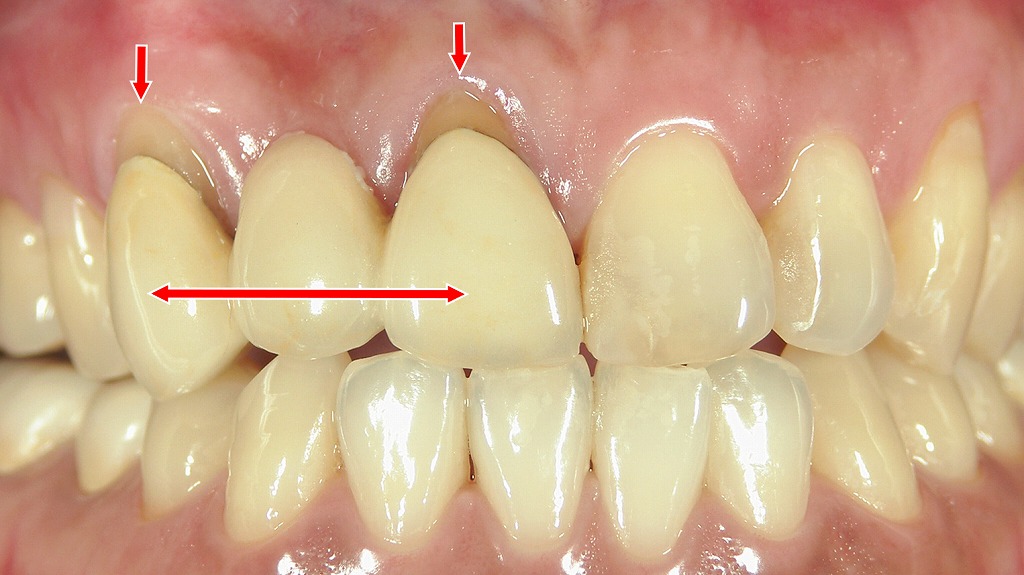

この写真は 右上1番・2番・3番がメタルボンドブリッジ(連結の被せ物)で補綴されている状態 を示しています。

● 歯肉退縮(矢印の部位)

赤い縦矢印で示された 右上1番・3番の歯肉が下がっており(歯肉退縮)、被せ物と歯ぐきの境目に段差や黒っぽい影が見えています。

歯肉退縮が起こる理由の代表例:

- 加齢による歯肉の薄さ

- ブラッシング圧が強い

- 咬み合わせや歯ぎしりによる負荷

- ブリッジ支台歯への長期的な力の集中

退縮が進むと、歯の根が露出したり、被せ物の境目が見えやすくなったりします。

● ブリッジの構造(横矢印の部位)

赤い横矢印は 1番〜3番が連結されているブリッジ であることを示しています。

2番をダミー歯として、1番と3番が支台歯となり、3本まとめて補綴されている典型的な構造です。

ブリッジ特有の特徴:

- 支台歯(1番・3番)に強い力が集中する

- 清掃が難しい箇所が増える

- 長期経過で歯肉退縮が起こりやすい

● 歯肉移植術で歯ぐきの厚み・高さを回復

右上1番・3番は歯肉が薄く下がっているため、

歯肉移植(遊離歯肉移植) を行うことで、

- 退縮した歯肉の高さの回復

- 歯肉のボリュームを増す

- メタルの影を見えづらくする

などの効果が期待できます。

特に前歯部では、厚みのある歯肉を確保することが審美性の改善に直結します。